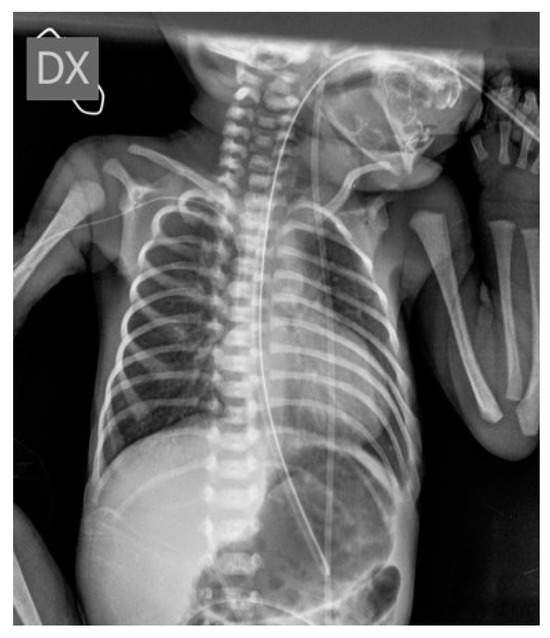

Conventional Radiology Evaluation of Neonatal Intravascular Devices (NIVDs): A Case Series

3. Results